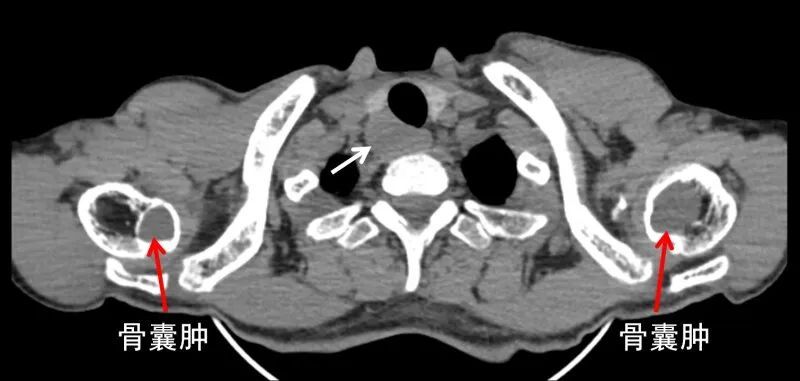

查看胸部CT横断面,可以看到双侧肱骨骨囊肿形成,同时还可以看到右侧甲状腺背后存在一个很明显的低密度软组织肿块(图4),这个才是真正的罪魁祸首,正是这个隐藏很深的甲状旁腺腺瘤持续分泌超高水平的甲状旁腺激素(PTH)引起一系列临床表现。

PTH就像一名勤劳的搬运工不断地把骨骼中的钙搬到血液当中,导致血钙升高,升高的血钙持续不断的从肾脏和尿液当中排除到体外,久而久之,骨骼中的钙被掏空,骨组织被大量纤维组织代替,甚至形成骨囊肿,这就是所谓的纤维囊性骨炎,因骨囊肿里面含有大量棕色的液体,因此又叫“棕色瘤”。

在经济发达和医疗资源丰富的地区,由于诊断意识和水平的提高,多数甲旁亢得到了早期诊断和早期治疗,这种典型的表现目前很难见到。另外还见到多处肋骨破坏(图5),这也属于甲旁亢引起的代谢性骨病,这种骨破坏很容易被误诊为恶性肿瘤骨转移。

图4.胸部CT:右侧甲状腺背后甲状旁腺腺瘤(白箭头),双侧肱骨骨囊肿(红箭头)

图5.胸部CT见多处肋骨破坏